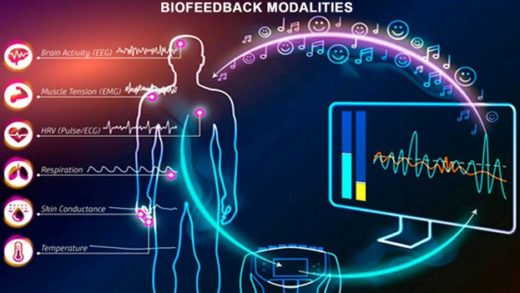

Check out this quick video about hydration and vitamins through IV therapy, then keep reading below for a full list of ways to boost your immune system quickly and naturally in Singapore.